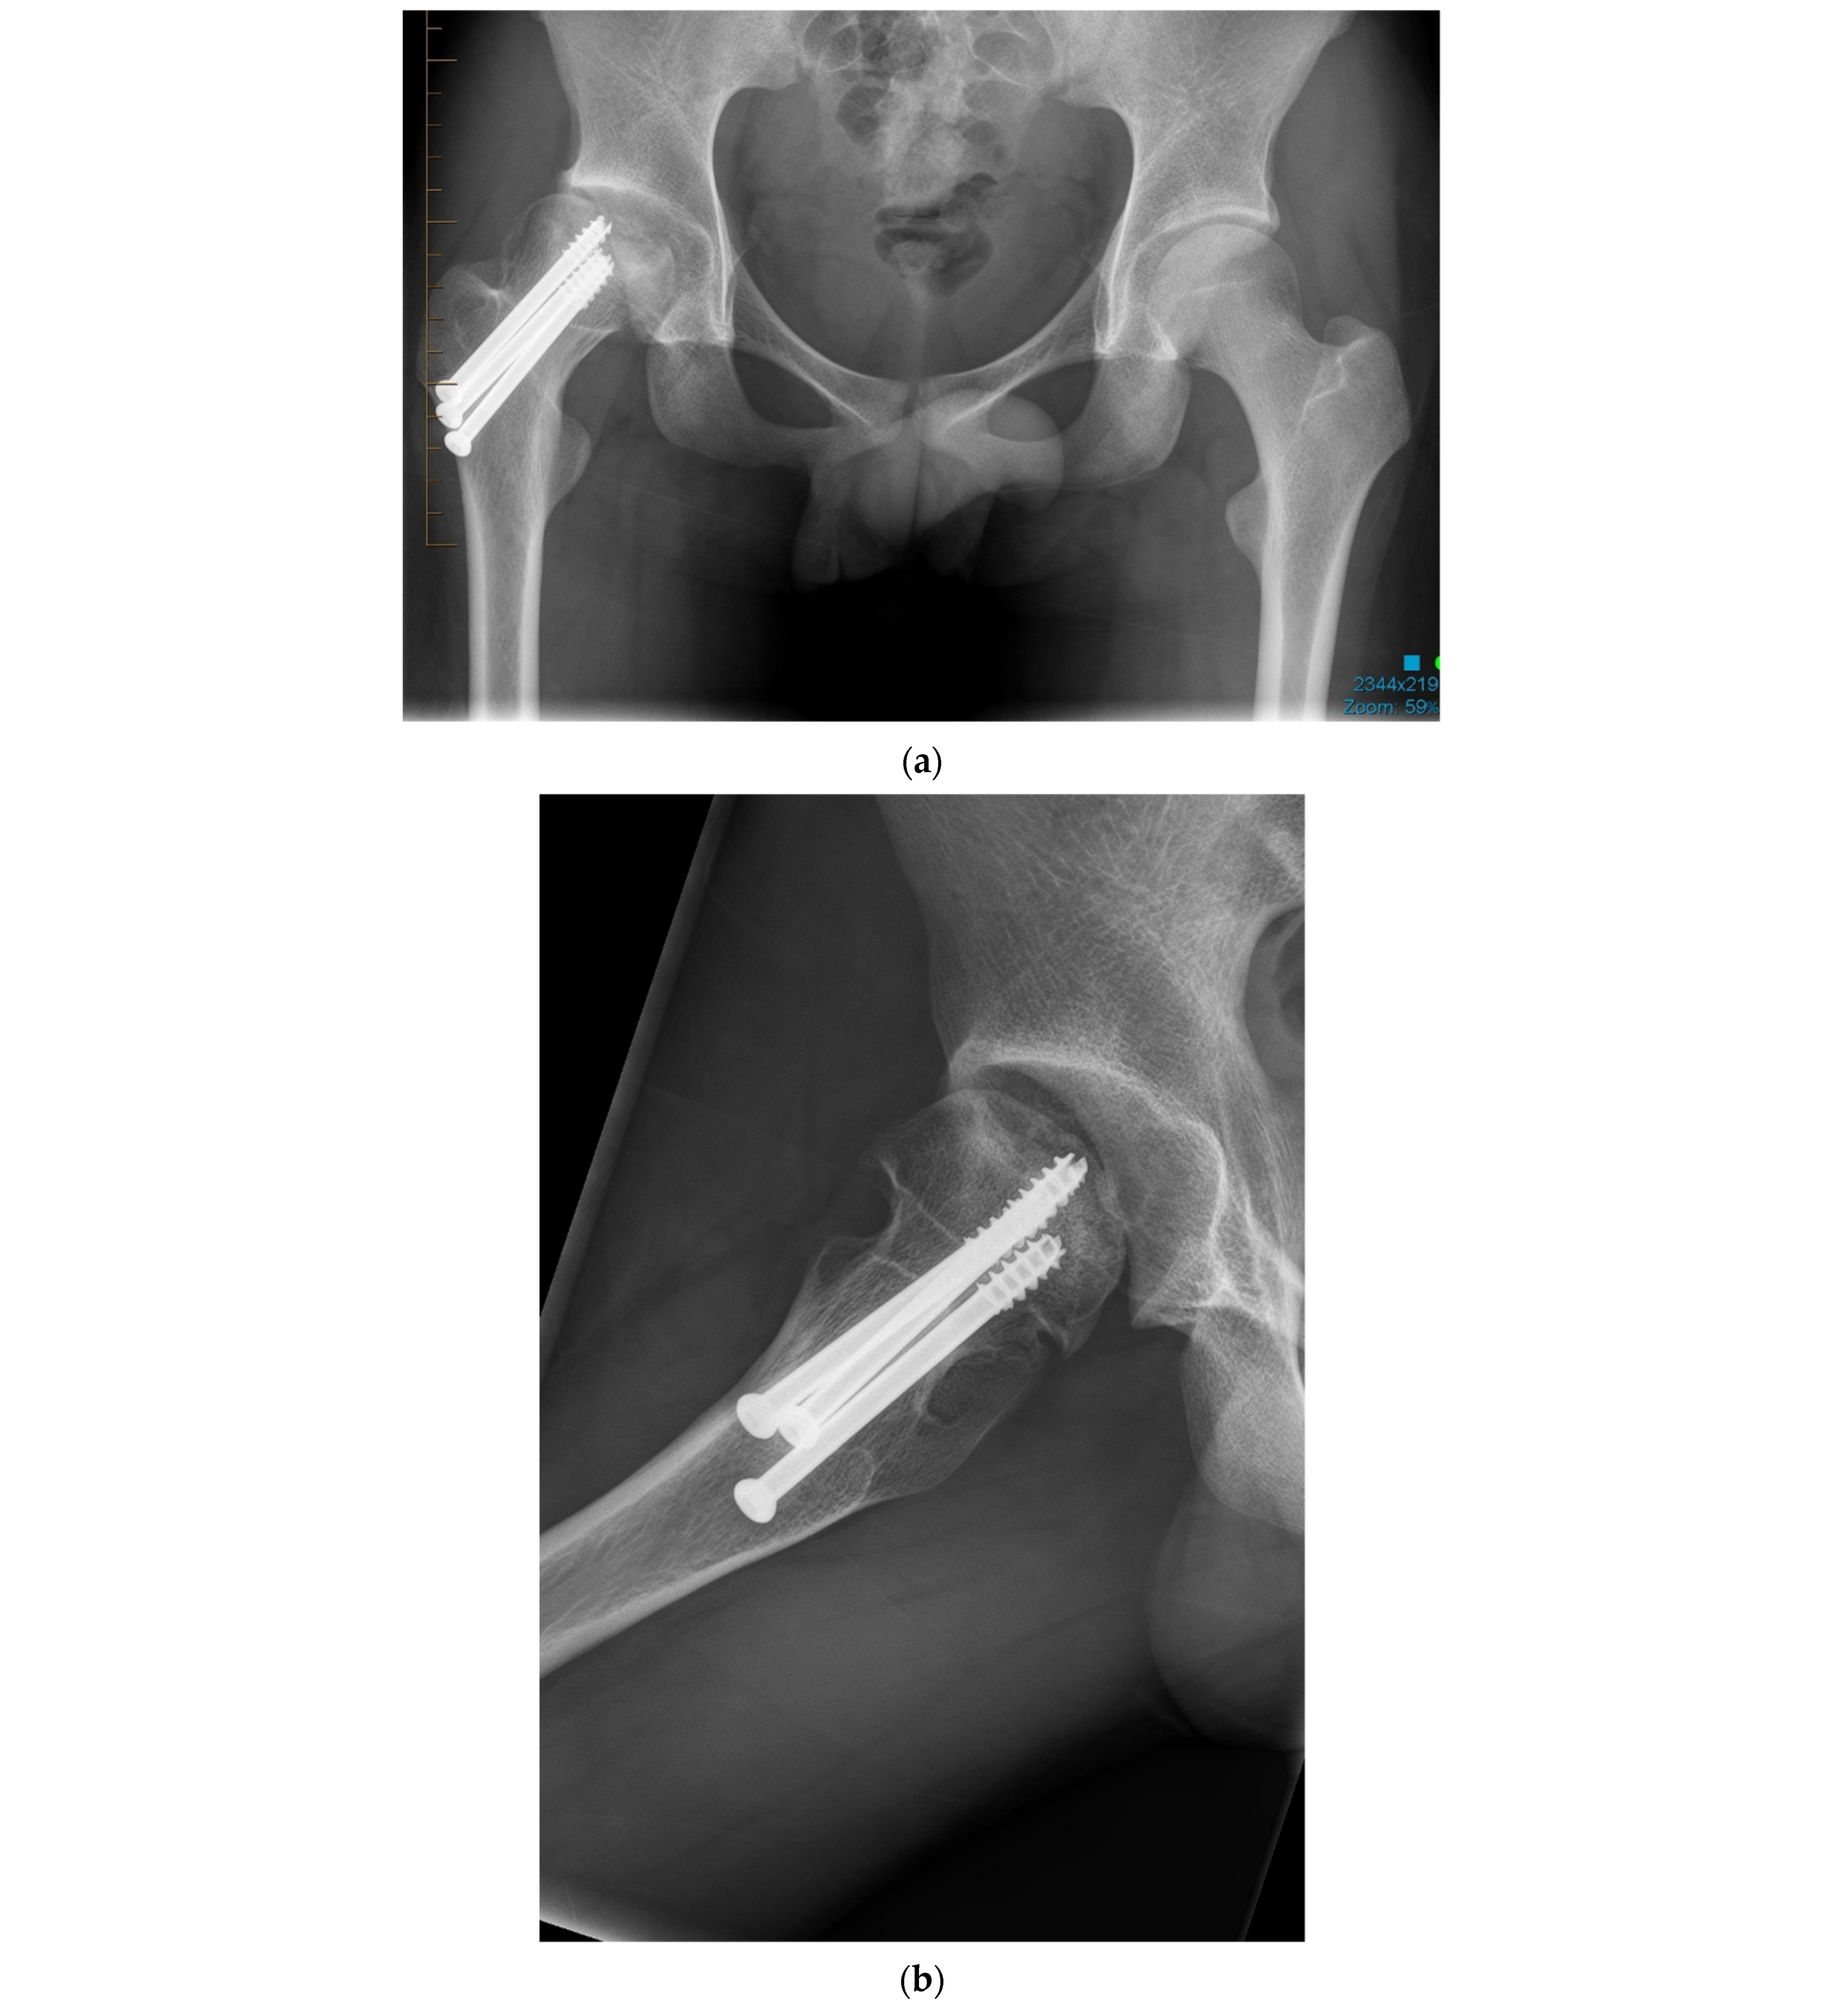

Figure 1.

(a) Anteroposterior pelvis radiograph of 19-year-old men with right femoral head avascular necrosis following a slipped capital femoral epiphysis treated with canulated screws. During preoperative templating, acetabular, and femoral components sizes were estimated to be small. (b) Preoperative lateral view of the right hip. (c) Postoperative anteroposterior pelvis radiograph showing a CoC LDH THA with a 13 mm conical stem and a 46 mm monobloc ceramic acetabular component with a bearing diameter of 36 mm. (d) Postoperative lateral view of the right hip replacement.